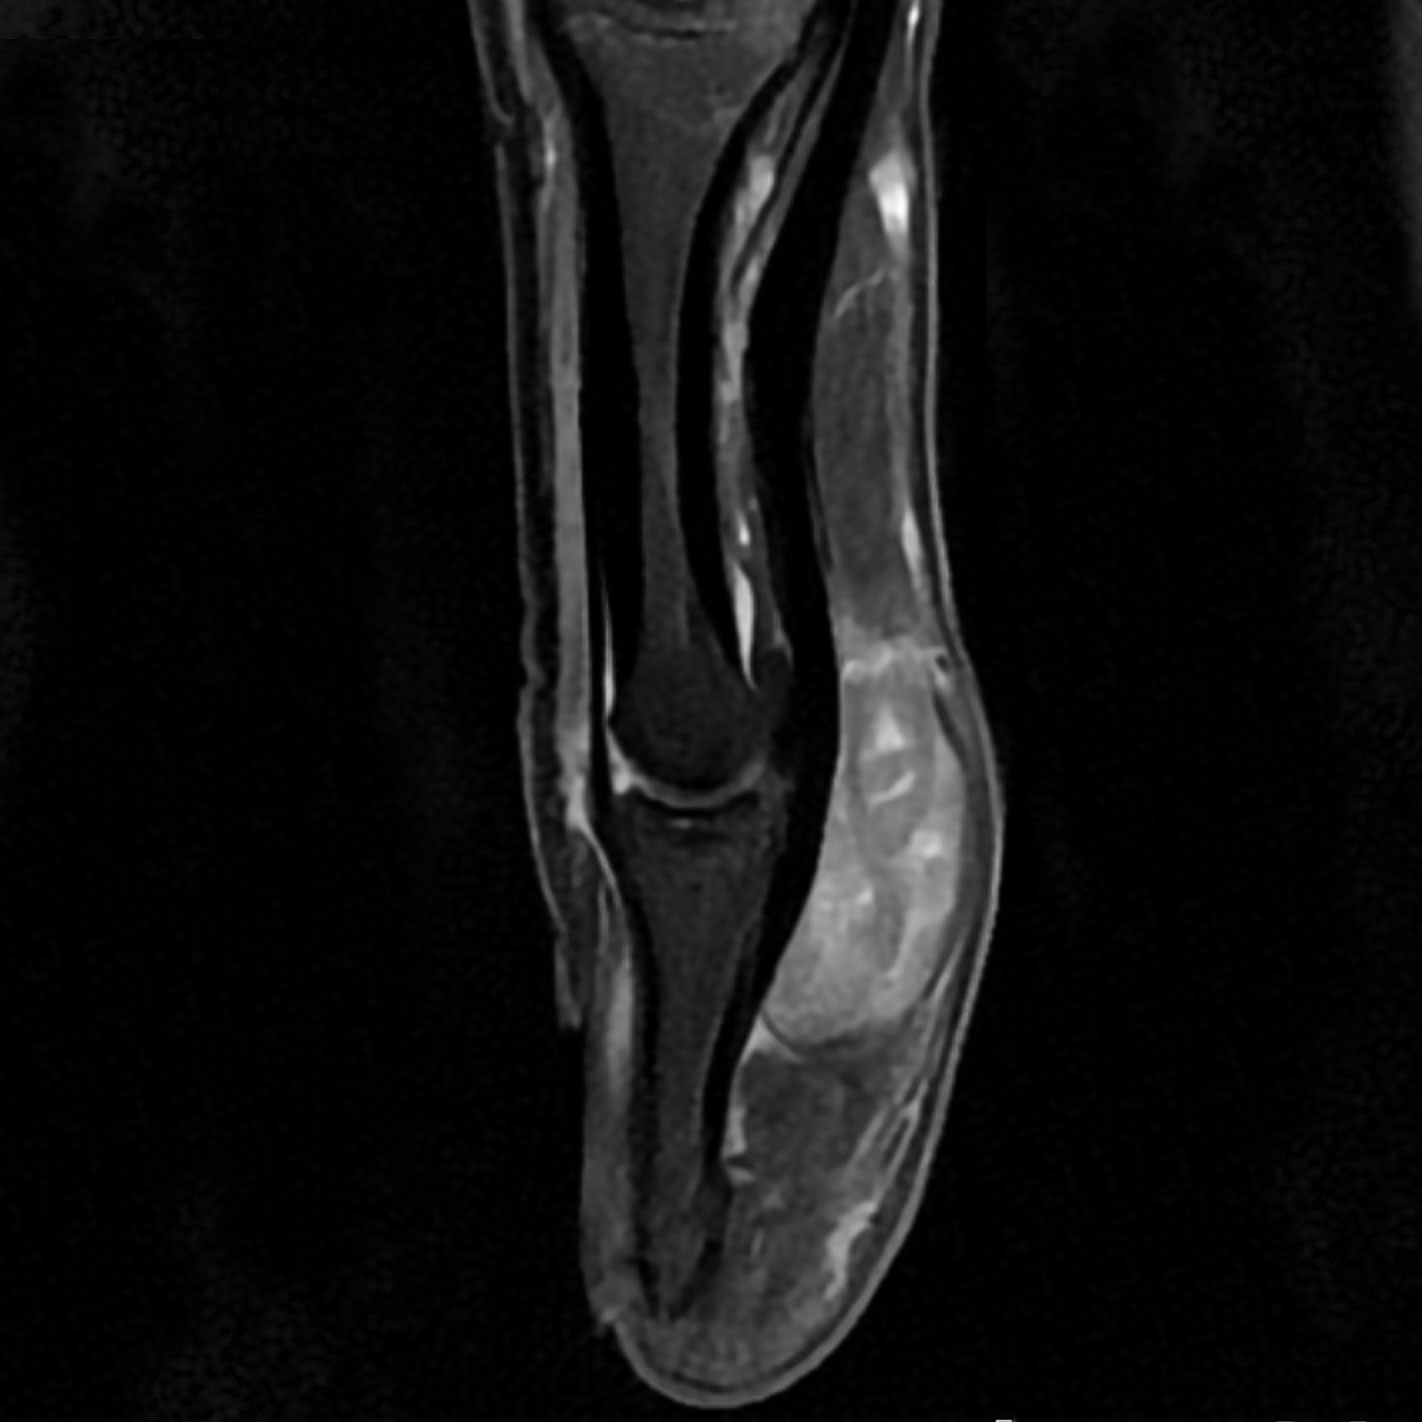

- du genou, le l'épaule, de la hanche et du bassin, du pied, de la cheville, des doigts, des articulations et des os.